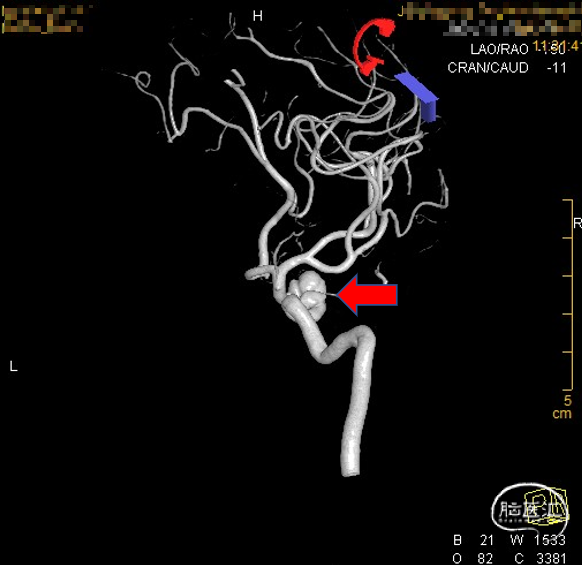

术前影像学资料

外院DSA

右侧颈内动脉眼动脉段-海绵窦段串联两枚动脉瘤,分别大小约:

① 8.8mm*5.9mm*5.2mm,瘤颈宽7.0mm;

② 6.8mm*4.3mm*3.6mm,瘤颈宽3.3mm。